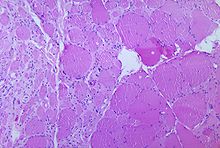

The destruction of neuronal cells produces lesions within the spinal ganglia; these may also occur in the reticular formation, vestibular nuclei, cerebellar vermis, and deep cerebellar nuclei. Inflammation associated with nerve cell destruction often alters the colour and appearance of the gray matter in the spinal column, causing it to appear reddish and swollen. Other destructive changes associated with paralytic disease occur in the forebrain region, specifically the hypothalamus and thalamus. The molecular mechanisms by which poliovirus causes paralytic disease are poorly understood.